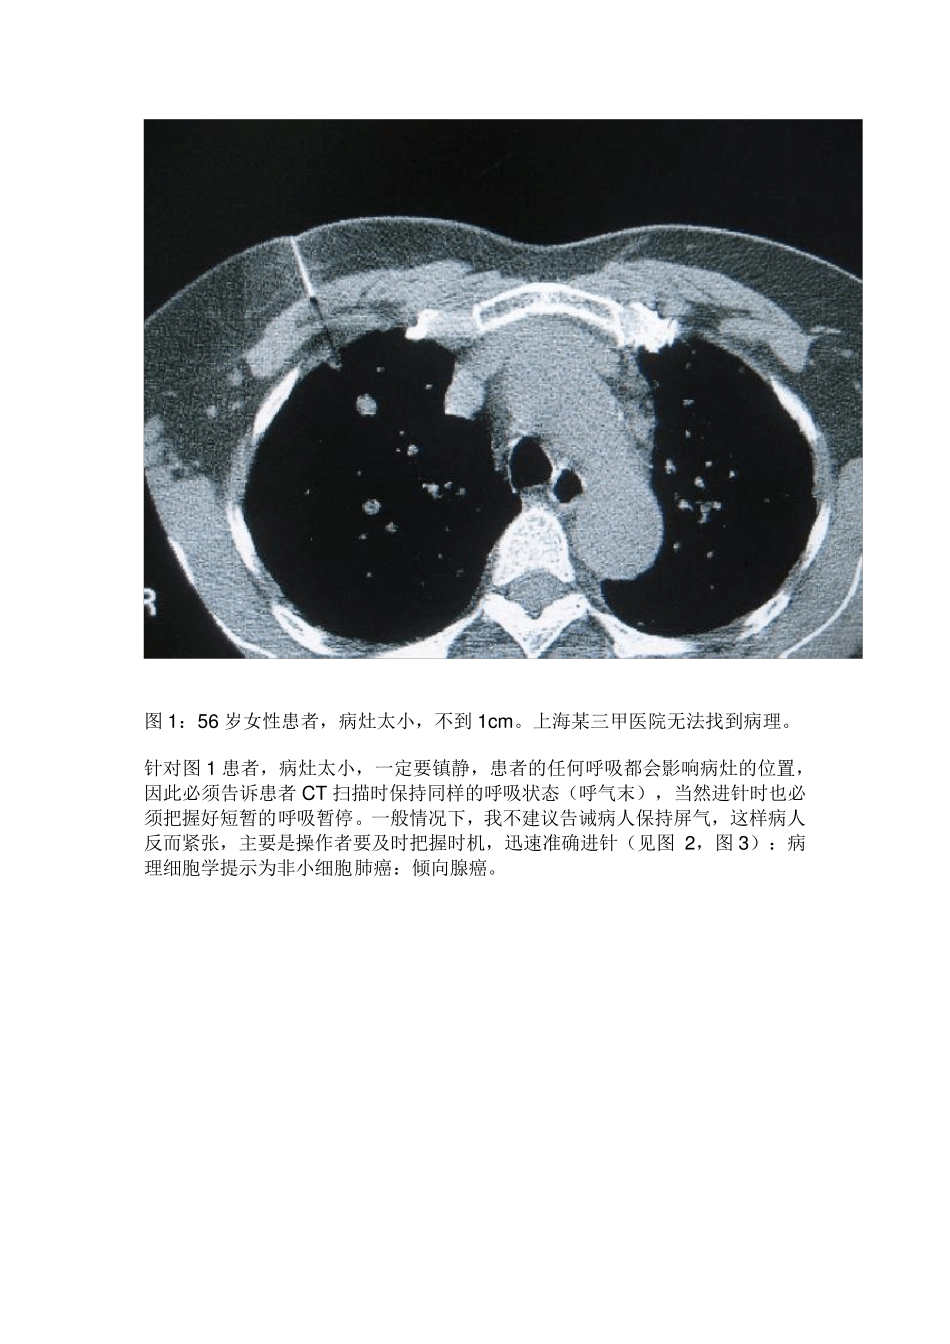

CT引导下经皮肺穿刺的几点心得 CT引导下经皮肺穿刺是肺部疾病的一种重要的诊断方法,当然也很老了,是指在CT扫描定位协助下,通过体外的穿刺针或活检枪对肺内病灶进行负压吸引或切割活检,取得病灶组织后送检来进行诊断和鉴别诊断的一种手段。 具体的操作步骤:在CT光标指示下,以记号笔标记出穿刺点,常规消毒、铺巾,局部麻醉后,穿刺针进入皮下后行CT扫描,直观地确定进针角度和病灶的关系后,按预定的进针角度和深度穿刺进针至靶点,再行靶层面 CT扫描,证实针尖位于病灶内,即负压吸引或活检枪击发取材。抽吸活检时抽吸针保持负压拨出,将内容物推到玻片上;组织针取出有形组织条送入 10%福尔马林液内固定。术后常规胸部CT扫描,观察有无气胸等并发症发生,如无不适,嘱患者回病房静卧 1-2 小时。 CT引导下经皮肺穿刺常见的并发症有气胸、肺出血、少量咯血和胸膜腔出血等。最常见的术后并发症主要为气胸和肺内出血,文献报告气胸发生率为 9%~44%,多在10%左右,大多是少量气胸,无需特殊处理休息吸氧后短时间可自行吸收,需做胸腔闭式引流的病人仅占 1.6%~14.3% ;肺内出血 1~3 日可自行吸收,少数病人有痰中带血;大咯血和胸膜腔出血的发生率较低。并发症的发生与操作者的熟练程度、进针次数、穿刺针与穿刺点胸膜切线位的角度及患者肺的质量如有无肺气肿等因素有关。 心得一:首先如何预防 CT引导下经皮肺穿刺的并发症? 1)首先术前进行患者教育,配合医生的操作,保持相同的呼吸状态。 2)正确地评估,要确定好穿刺层面和进针点,以及进针深度、角度和呼吸对穿刺的影响。穿刺点到病变距离最短,以垂直方向或水平方向为佳。尽量避开叶间胸膜、肺大疱及 CT 下能显示的粗大血管影或肺纹理等。 3)麻醉针不宜穿刺太深,若刺破胸膜,会增加气胸的概率。 4)穿刺胸膜时,病人应在平静呼气后屏气状态下进行,动作迅速地刺入靶点,尽量缩短穿刺经过胸膜的时间。 5)穿到细胞或组织后,应在呼气末负压迅速拔出穿刺针。 心得二:如何穿到肿瘤组织内。 当然,常规的、较大的、贴近胸膜的病灶是不用说的,要讲的是小病灶、骨组织后的难以取得的病灶或靠近大血管病灶和肺气肿患者。 1)小病灶 图1:56 岁女性患者,病灶太小,不到1cm 。上海某三甲医院无法找到病理。 针对图1 患者,病灶太小,一定要镇静,患者的任何呼吸都会影响病灶的位置,因此必须告诉患者CT 扫描时保持同样的呼吸状态(呼气末),当然进针时也必...